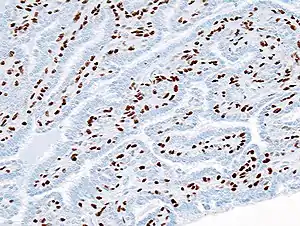

Histopathology of intraductal papilloma of the breast by excisional biopsy. Immunostaining for p63 protein.